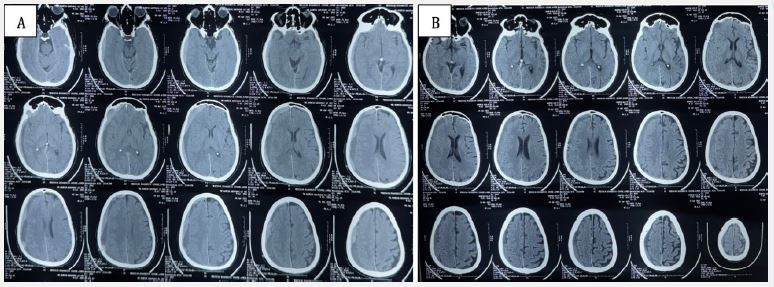

Two weeks later, the patient re-presented with acute-onset holocranial headache for 5 days, severe and non-responsive to analgesics. Repeat NCCT head showed recurrent subacute SDH with acute elements along the same right convexity (Figure 2A). There was no fresh trauma. Given the recurrence and cardiac comorbidity, he was referred to interventional neuroradiology, and underwent middle meningeal artery embolization (MMAE) on April 8, 2025.

The procedure was uneventful, and the patient remained neurologically stable postoperatively with no new deficits. On April 22, 2025, follow-up NCCT showed partial resolution of the hematoma with no fresh bleed (Figure 2B). The patient was asymptomatic and neurologically intact.

Figure 2: (A) Pre embolization NCCT head acute on subacute subdural hemorrhage seen along the right cerebral convexity in right parietal region. Mass effect noted in the form of effaced adjacent sulci and ipsilateral lateral ventricle with subfalcine herniation and contralateral mid line shift.

(B) Post MMA embolization NCCT head showing partial resolution of acute bleed with decrease in mass effect.